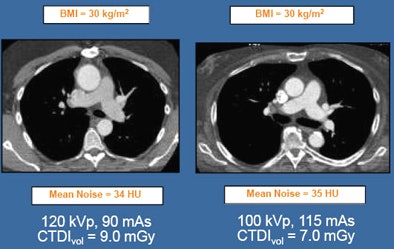

In the absence of real standards, kVp levels are usually based on visual assessment of patient size. Sometimes more objective measures such as patient weight and body mass index are used. Several studies, mostly from Europe, have suggested 100 kVp for patients weighing 85 kg or less. One group recommends 80 kVp for patients weighting 60 kg or less.

The studies represent a kind of standard that radiologists can look to in the absence of true guidelines, Halliburton said.

| Studies support the use of low-kVp cardiovascular imaging. All images courtesy of Sandra Halliburton, Ph.D. |